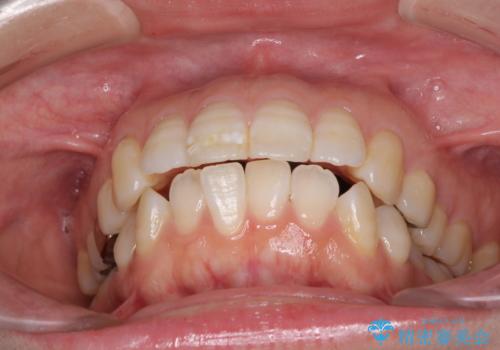

積極的に前歯を牽引したことで、口元の閉じにくさは顕著に改善され、横顔のシルエットが大幅に変化しました。